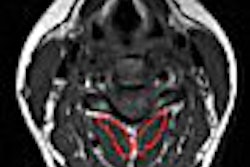

In our previous Insider, we looked at the value of MRI and ultrasound for assessing tenosynovitis, skier's thumb, and vascular flow. Today's Insider Exclusive article offers a different perspective on wrist imaging -- MR arthrography for triangular fibrocartilage tears and instability. Click here to learn more.